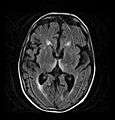

Axial MRI FLAIR image showing hyperintense signal in the mesial dorsal thalami, a common finding in Wernicke encephalopathy. This patient was nearly in coma when IV thiamine was started, he responded moderately well but was left with some Korsakoff type deficits.

Axial MRI B=1000 DWI image showing hyperintense signal indicative of restricted diffusion in the mesial dorsal thalami.

Axial MRI FLAIR image showing hyperintense signal in the periaqueductal gray matter and tectum of the dorsal midbrain.